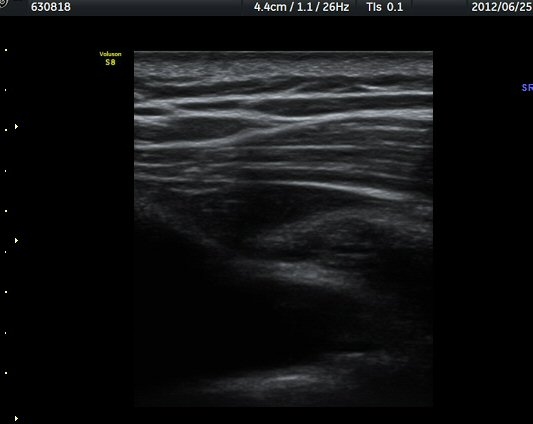

¾î±ú °üÀý µÚÂÊ ÈĹæ°üÀý¼ø Ⱦ´Ü¸é°Ë»ç¿¡¼­ °üÀý¼ø ³»Ãø, °¡½Ãµ¹±â°üÀý¼ø°í¶û(spinoglenoid

notch)¿¡¼­ Àú¿¡ÄÚ ³¶Á¾ÀÌ °üÂûµÈ´Ù(±×¸² 1). ŽÃËÀÚ¸¦ À§-¾Æ·¡ ¹æÇâÀ¸·Î º¯°æÇÏ¿© °üÂûÇÒ ¶§µµ

¿ª½Ã °ß°©°ñ °¡½Ãµ¹±â(spine) ¾Æ·¡¿¡¼­ Àú¿¡ÄÚ ³¶Á¾ÀÌ °üÂûµÈ´Ù(±×¸² 2). º¼·ÏŽÃËÀÚ·Î ¹Ù²Ù¾î °ü

ÂûÇÏ´Ï  °¡½Ãµ¹±â°üÀý¼ø°í¶û¿¡¼­ Àú¿¡ÄÚ ³¶Á¾ÀÌ ´õ¿í ¶Ñ·ÈÈ÷ °üÂûµÈ´Ù(±×¸² 3, 4).